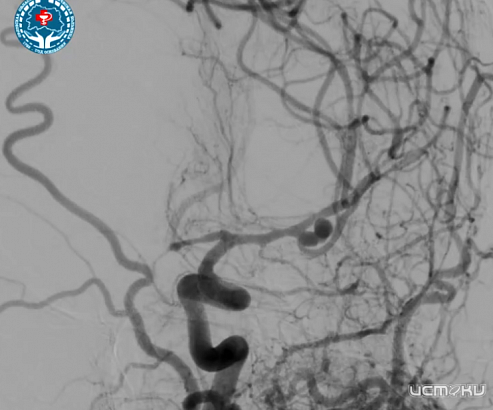

В нейрореанимационное отделение Орловской областной клинической больницы был доставлен 63-летний мужчина с рецидивом субарахноидального кровоизлияния. Диагностика показала наличие мешковидной аневризмы со сложной анатомией и несколькими полостями в среднемозговой артерии. Это состояние угрожает жизни пациента и нуждается в неотложной медицинской помощи. Имелся риск повторного разрыва аневризмы, после которого пациент мог остаться инвалидом или умереть. После консилиума было решено провести высокотехнологичную операцию – эмболизацию аневризмы с использованием микроспиралей.